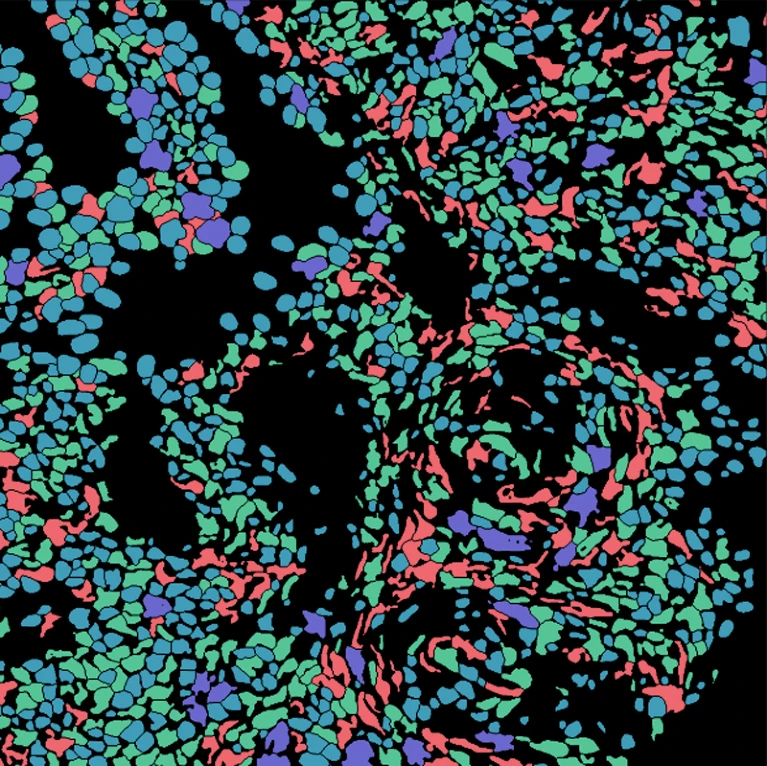

如果你想从细胞图像中提取数据,那你必须知道细胞在图像中的实际位置,这一过程也称为细胞分割(cell segmentation)。

研究人员需要在显微镜下观察细胞,或者在软件中一张一张地勾勒出细胞的轮廓

加州理工学院的计算生物学家Morgan Schwartz正在寻求自动化处理的方法,随着成像数据集变得越来越大,传统的手工方法也遇到了瓶颈,有些实验如果不自动化就无法进行分析

Schwartz的研究生导师、生物工程师David Van Valen创建了一套人工智能模型,并发布在了deepcell.org网站上,可以用来计算和分析活细胞和保存组织图像中的细胞和其他特征。

Van Valen与斯坦福大学癌症生物学家Noah Greenwald等合作者一起还开发了一个深度学习模型Mesmer,可以快速、准确地检测不同组织类型的细胞和细胞核

据Greenwald说,研究人员可以利用这些信息来区分癌症组织和非癌组织,并寻找治疗前后的差异,或者基于成像的变化来更好地了解为什么一些患者会有反应或者没有反应,以及确定肿瘤的亚型。